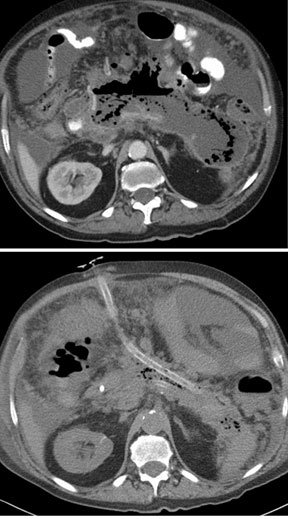

5.3 cm diameter hepatocellular carcinoma in segment 7 of the right hepatic lobe was treated twice with TheraSphere in a subsegmental fashion (“radiosegmentectomy”). The second CT was taken 8 months after the first radioembolization procedure. 12 months after the first radioembolization, his medical condition improved to allow a right hepatectomy. The pathologic specimen revealed no residual carcinoma in the resected liver.